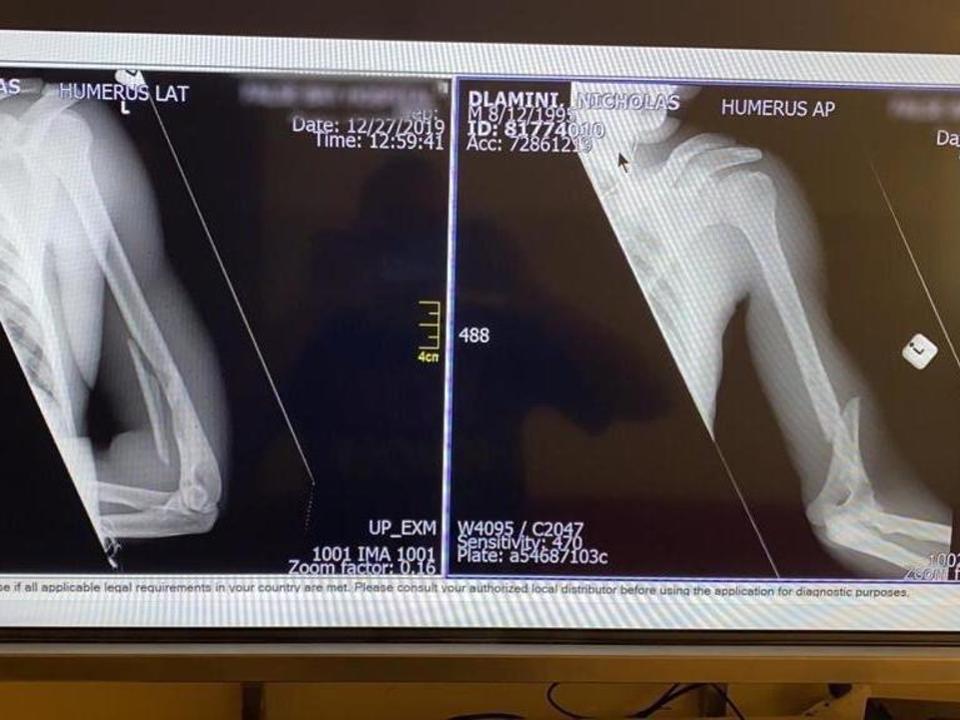

“NTT Pro Cycling confirma que el ciclista Nicolas Dlamini ha sufrido una fractura en el brazo después de ser detenido por funcionarios de SANParks en la zona Silvermine del Parque Nacional de Table Mountain, este mismo jueves.

Este es un revés importante para el joven ciclista, que se encontraba en pleno campus de preparación para un prometedor 2020.